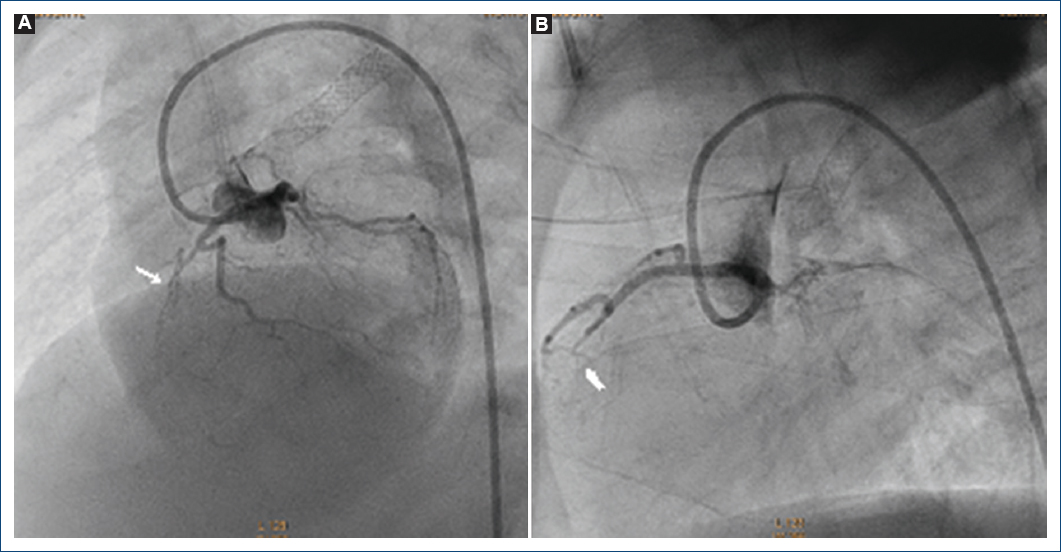

Figura 5 Ventriculografía derecha proyección postero-anterior. A: se observa atresia pulmonar con septum ventricular íntegro con conexiones ventrículo-coronarias con insuficiencia tricuspídea generada por el catéter angiográfico (flecha). B: al retirar el catéter angiográfico desparece la insuficiencia tricuspídea.